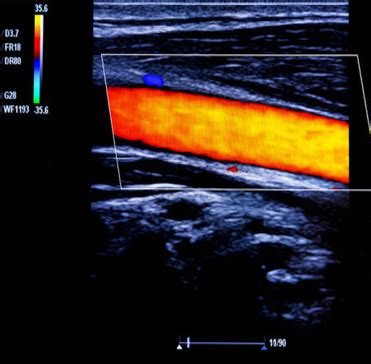

Alright, let’s get to the nitty-gritty of what Doppler ultrasound actually is. At its core, it’s a non-invasive medical imaging technique that uses sound waves to create images of blood flow inside your body. Think of it like a super-powered sonar for your veins and arteries! It’s a variation of the standard ultrasound we often associate with pregnancy scans, but with a special twist. The ‘Doppler’ part refers to the Doppler effect, a phenomenon that describes the change in frequency of a wave (in this case, sound waves) when the source of the wave and the observer are moving relative to each other. In medical terms, this means the ultrasound machine sends sound waves into your body, and when these waves bounce off moving red blood cells, their frequency changes. The ultrasound machine then detects this change in frequency, which allows it to measure the speed and direction of blood flow. Pretty cool, right? This ability to visualize and quantify blood flow is what makes Doppler ultrasound indispensable for diagnosing conditions like DVT, where the problem isn’t just the presence of a clot, but how that clot is affecting the normal circulation of blood.

Now, let’s talk about the star of the show: how Doppler ultrasound specifically helps us spot Deep Vein Thrombosis (DVT). DVT occurs when a blood clot, usually in a deep vein of the legs, blocks blood flow. This is serious business, as the clot can break off and travel to the lungs, causing a pulmonary embolism (PE), which is a life-threatening condition. Doppler ultrasound is the gold standard for diagnosing DVT because it can directly visualize these clots and, crucially, assess the impact on blood flow. The procedure typically involves a trained sonographer applying a gel to your skin over the suspected area (usually the legs) and then moving a transducer, a handheld device, over the skin. This transducer emits high-frequency sound waves. As these waves travel through your body, they bounce off various tissues and structures, including your blood vessels and the red blood cells within them. The machine listens to the returning echoes. In areas without a clot, the sound waves will reflect off the moving blood cells predictably, showing a normal flow pattern. However, when a clot is present, it can partially or completely block the vein. This blockage will alter the sound wave reflections in several ways:

1. Direct Visualization of the Clot: In many cases, the clot itself can be seen as an echogenic (bright) material within the vein, obstructing the normal lumen (the open space where blood flows). The sonographer looks for a lack of compressibility of the vein; a healthy vein will flatten when gentle pressure is applied by the transducer, but a vein filled with a clot will remain rounded.

2. Altered Blood Flow Patterns: This is where the ‘Doppler’ part really shines. The machine detects changes in the frequency of the returning sound waves. If blood flow is reduced or absent in a segment of the vein due to a clot, the Doppler signals will be weaker or absent altogether. The sonographer will assess ‘phasicity’ (the normal rhythmic changes in blood flow related to breathing) and ‘compressibility’ of the veins. A clot disrupts these normal flow characteristics.

By combining these findings—visualizing the clot, assessing compressibility, and analyzing the Doppler signals for flow abnormalities—doctors can confidently diagnose DVT. It’s a powerful tool because it provides real-time information about the health of your venous system, helping to guide treatment decisions and prevent serious complications.